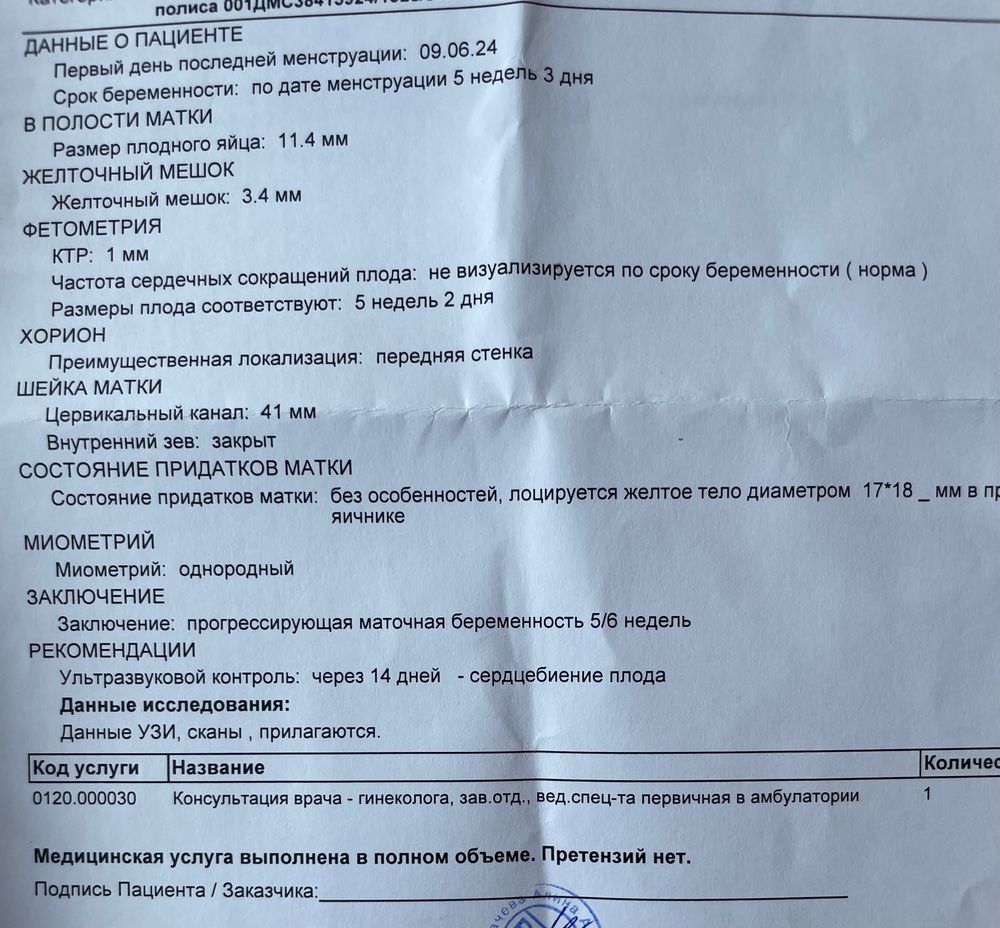

24 ДПО. Он же 3 день 5 недели. УЗИ и ТТГ

1. Режим паникер активен. Чувствую дискомфорт в животе - паника, ничего не чувствую - паника. В итоге не удержалась и пошла вновь на УЗИ. Вс] отлично, увидели и ЖМ, и даже очень маленький эмбриончик. Ура! Надо обуздать свои переживалки и спокойно посидеть две недели.